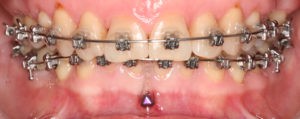

Искривление окклюзионной кривой (плоскости смыкания зубов), возникшее в результате парадонтита, успешно удалось устранить, используя накусочные брекеты на верхних резцах и микроимплант, установленный во фронтальном участке нижней челюсти: